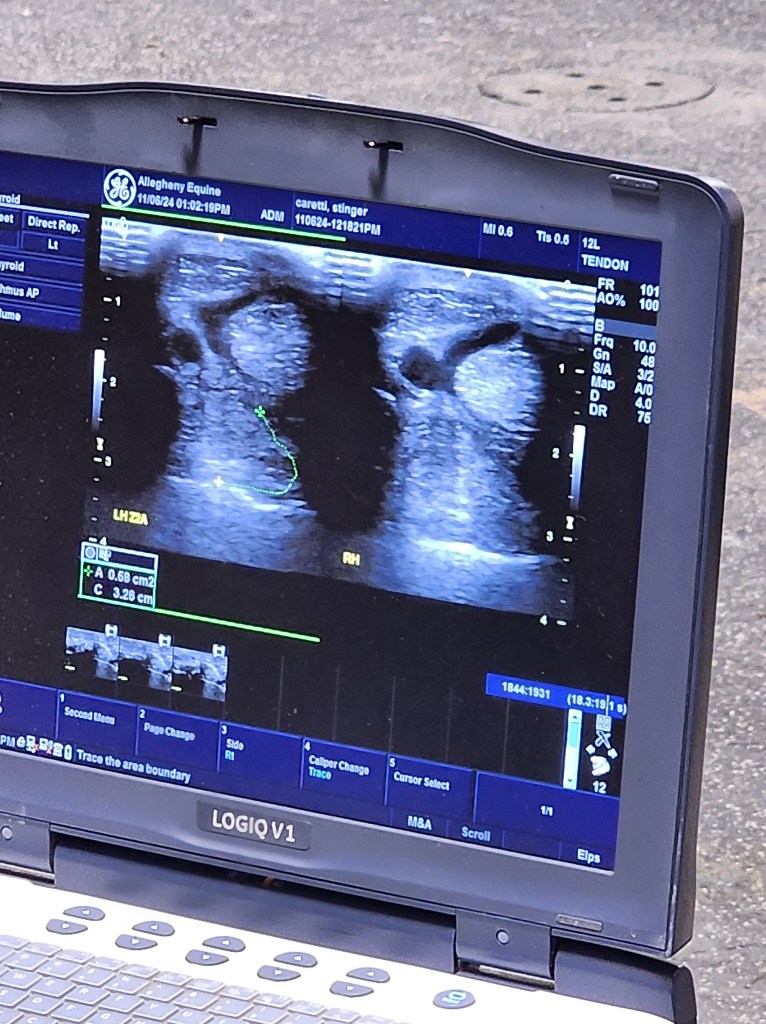

It ended up being four weeks from the initial injury until we got to the appointment on November 6th. We started off with a repeat lameness exam to see where the problem is. Because we knew he had hurt his hock, we opted to perform nerve blocks to see exactly where the problem was. After the first block in the fetlock, there was no improvement. The tarsocrural joint (large hock joint) was next with almost 80% improvement after 15 minutes. The next step was to ultrasound the hock and suspensory ligament. All the ligaments in the hock were normal, but the suspensory ligament was enlarged by 30% and had a tear, his hock joint also had some inflammation. I wasn’t sure what to expect when going to this appointment, I honestly thought maybe his hack was fractured. I just never thought it would be a suspensory tear. The unbelievable part was the vet did not think this was a new injury. We do think he just sprained his hock while he was playing but he didn’t cause the tear the month before. It just took this long to diagnose and his accident in the pasture just helped us finally find the problem. It also helps explain why we could ride at home and have no problems, but couldn’t complete a pattern at a show. Our ring is hard and rocky, with no loose dirt and we believe the deeper soft ground at shows was making him have pain and struggle to make a right turn.

Now for the treatment plan. We opted to have a PRP injection and shockwave therapy while we were there that day. The PRP injection was cool to see, they took some of his own blood, spun it, and injected it back into his leg. The shockwave was really loud, but he was still sedated so it didn’t bother him. Since we live in Pennsylvania, we will do a series of shockwave treatments in the spring and then have him rechecked with another ultrasound. Until then, the vet recommended stall rest in a large stall (which we just happened to have built while fixing the barn, a weird coincidence) and shoes with heel extensions. I also bought him a red-light therapy boot, so I can put it on him at home a couple times a week to help with healing.